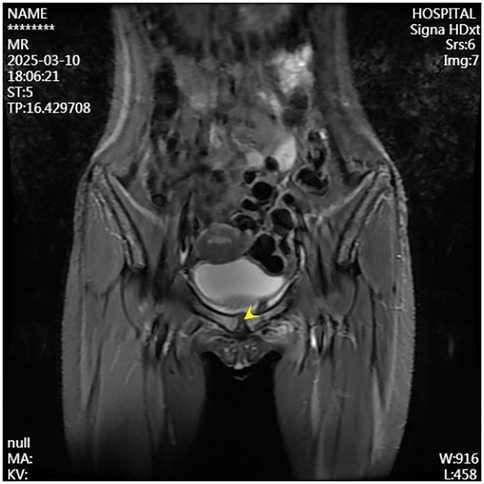

A second surgical procedure was performed four days later. This involved VCS implantation, repeat debridement of the pubic symphysis, and bilateral pubic bone fenestration with drainage. During the procedure, 2 grams of vancomycin powder were combined with 5 milliliters of Stimula® calcium sulfate powder and 2.6 milliliters of sterile water for injection. Following approximately 30 s of thorough mixing, a homogeneous paste was achieved. This paste was subsequently placed into a mold to form hemispherical beads with a diameter of 4.0 millimeters. The antibiotic beads were allowed to set for approximately 15 min before being extracted from the mold for intraoperative application. Under fluoroscopic guidance, the beads were implanted into the medullary cavity. Once the cavity was confirmed to be adequately filled, additional VCS beads were applied to cover the cortical surface of the bone window and the defect area, thereby restoring the structural contour of the local bone. Postoperative serum vancomycin levels were assessed every three days starting from the first postoperative day, with dosage adjustments made based on pharmacokinetic analysis to ensure concentrations remained within the target therapeutic range. Concurrently, routine evaluations of hepatic and renal function, electrolytes (including calcium), and superficial ultrasound examinations of the surgical site were conducted, which revealed no significant fluid accumulation. Laboratory results were within normal limits: white blood cell count at 6.01 × 109/L, neutrophil percentage at 54.3%, C-reactive protein at 2.43 mg/L, procalcitonin levels below 0.1 ng/ml, erythrocyte sedimentation rate at 10 mm/h, negative blood cultures, and normal hepatic and renal function, electrolytes, and calcium levels. The patient had no relevant postoperative symptoms such as frequent urination, urgent urination, hematuria, or dysuria.By one week postoperatively, the surgical incision had healed by primary intention, pain at the pubic symphysis had fully resolved, and lower limb motor function had returned to normal, with full hip abduction and internal rotation. Imaging conducted at two weeks post-surgery revealed the presence of residual antibiotic beads and localized infection with osteolytic defects in the pubic symphysis (Figures 4, 5). Following discharge, the patient underwent a four-week regimen of oral vancomycin aimed at eradicating any residual infection and was advised to refrain from engaging in strenuous activities for three months. Subsequent imaging at the six-week mark revealed complete absorption of the calcium sulfate artificial bone, resolution of prior infectious indicators, and a visible periosteal reaction indicative of active bone remodeling (Figures 6, 7). By the 22-week follow-up, callus formation was evident in the bilateral pubic rami, signifying successful osseous healing (Figure 8).

Figure 6. Follow-up MRI at six weeks postoperatively demonstrates resolved infection at the pubic symphysis.

Figure 7. Follow-up pelvic radiograph at six weeks postoperatively shows absorption of the artificial bone and noticeable periosteal reaction.